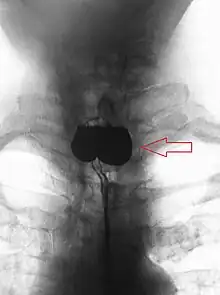

En anatomie, un diverticule de Zenker est un diverticule (une poche) de pulsion qui se forme au-dessus du sphincter œsophagien supérieur entre le faisceau thyroïdien du muscle constricteur inférieur et le faisceau cricoïdien du muscle constricteur inférieur (aussi appelé muscle cricopharyngien).

Radiographie où on voit une diverticule de Zenker.

Le diagnostic est radiologique. Aujourd'hui l'imagerie de première intention à effectuer est un scanner cervico-thoraco-abdomino-pelvien avec opacification digestive haute ainsi qu'injection de produit de contraste. Le transit œso-gastro-duodénal historiquement utilisé qui visualise le diverticule sous forme d'une image d'addition du tiers supérieur de l'œsophage n'a pratiquement plus d'indication à l'heure actuelle en raison de la meilleure précision de l'examen TDM[1].